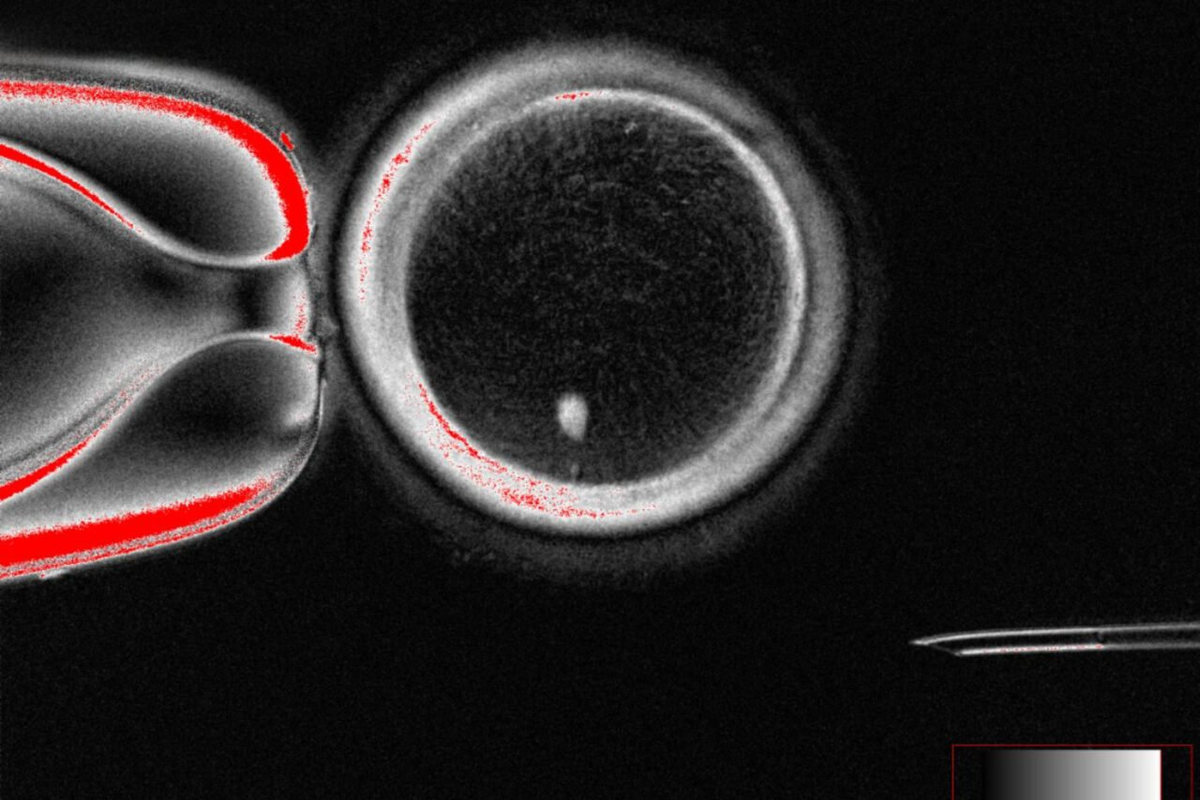

Одна из перепрограммированных яйцеклеток, вид до оплодотворения